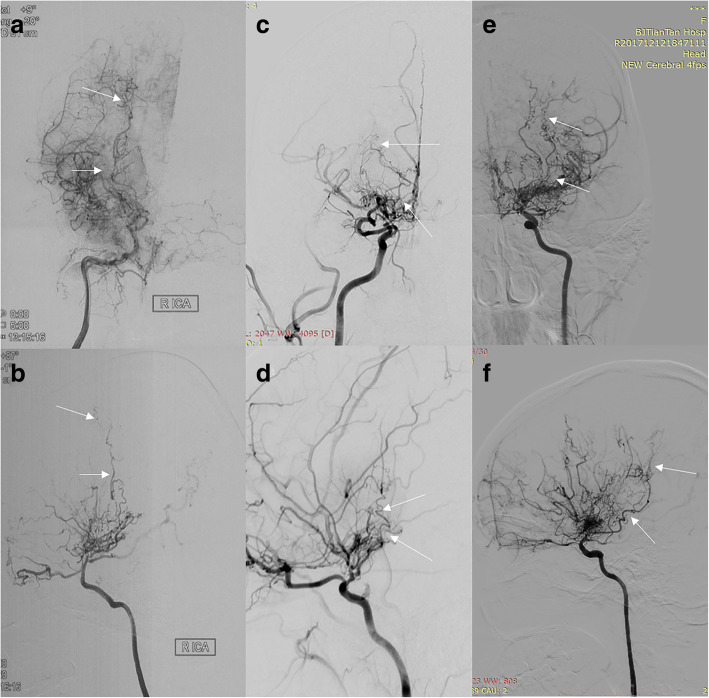

Collateral vessels were classified into three subtypes according to origin [8]: lenticulostriate anastomosis, thalamic anastomosis, and choroidal anastomosis. Lenticulostriate anastomosis (Fig. 1a-b): an anastomosis between the lenticulostriate artery and the medial end of the medullary artery with at least 1 artery extending beyond the level of the pericallosal artery in the lateral view. Thalamic anastomosis (Fig. 1c-d): an anastomosis between the thalamic perforator and the medial end of the medullary artery or the insular artery with at least 1 perforator extending beyond the position of the medial posterior choroidal artery in the lateral view. Choroidal anastomosis (Fig. 1e-f): an anastomosis between the choroidal artery and the medial end of the medullary artery with choroidal artery deviated from the level of the lateral ventricle.

Fig. 1.

Collateral vessels. a, anteroposterior view of lenticulostriate anastomosis; b, lateral view of lenticulostriate anastomosis; c, anteroposterior view of thalamic anastomosis; d, lateral view of thalamic anastomosis; e, anteroposterior view of choroidal anastomosis; f, lateral view of choroidal anastomosis